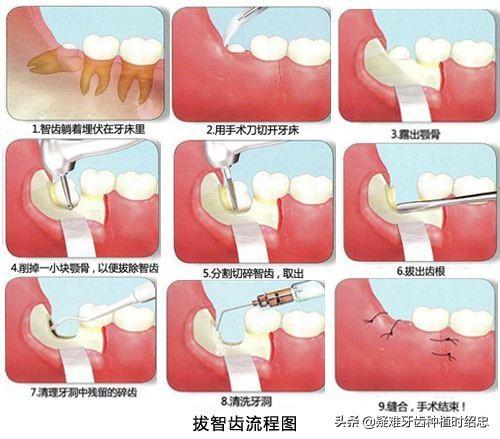

拔智齿后那个洞臭到恶心(拔智齿后嘴里恶臭是什么情况?)

拔智齿后那个洞臭到恶心(拔智齿后嘴里恶臭是什么情况?)

干槽症是怎么发生的?

干槽症是拔牙所导致急性感染的一种,多发生在下颌智齿拔除后,由于口腔细菌引起的骨创伤感染,其它牙齿少见。

干槽症公认原因是拔智齿时创伤、伤口过大

,(比如上文所说的那样,拔牙时间过长,或为了更好的手术视野把牙龈切开,术后又缝合不理想等原因),

所引起的继发感染

。因此,为了预防干槽症的发生,在拔牙过程中应尽量减少创伤,拔牙后应尽量缩小拔牙创口;拔牙前后可以使用抗生素,预防感染。